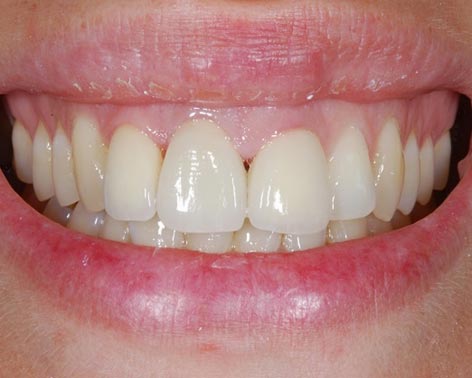

Faccette estetiche in ceramica